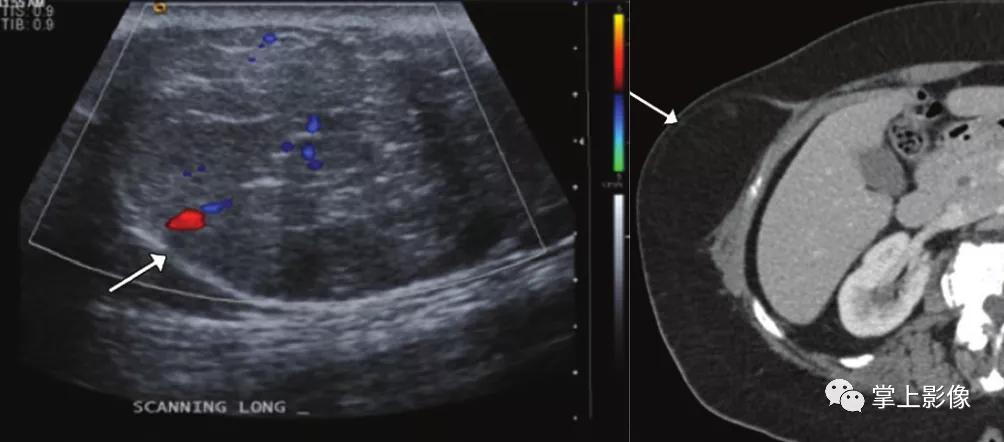

81岁女性接受系统抗凝治疗的直肌鞘血肿。超声(A)和轴位CT(B)图像示右直肌鞘内血肿内红细胞压迹(虚线箭头)和活动性外渗(b中实心箭头)